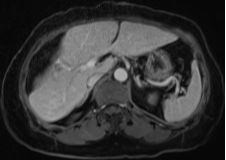

結(jié)腸腫瘤是指發(fā)生在結(jié)腸部位的腫瘤,可分為良性和惡性,結(jié)腸腫瘤早期癥狀不明顯,隨著病情發(fā)展,可能出現(xiàn)腹痛、便血、腸梗阻等癥狀,治療方法包括手術(shù)、化療、放療等,具體治療方案需根據(jù)患者的具體情況制定。